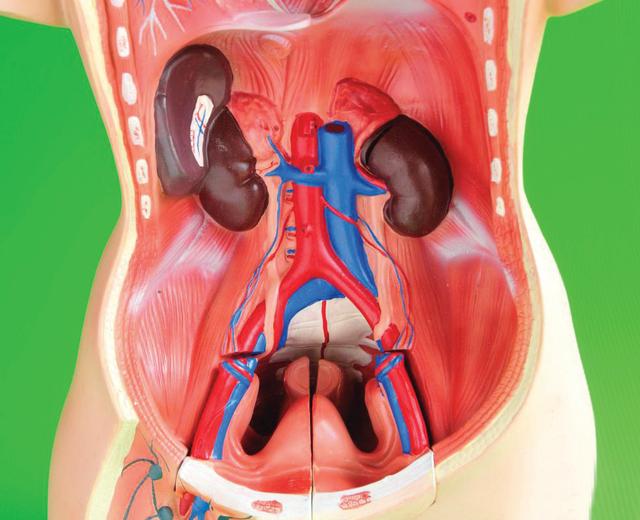

هو أقل شيوعاً بكثير ولكنه يمكن أن يحدث في الرجال الذين يعانون تضخم البروستاتا أو في النساء إثر جراحة بالحوض. فنتيجة للانسداد الجزئي، لا تتمكن المثانة من التفريغ التام، وقد يقطع البول بشكل متكرر. وقد يحدث أيضاً عندما تصبح المثانة شديدة الضعف بسبب مشكلات عصبية.

بعد أن يطلع الطبيب على تاريخه المرضي كي يستبعد الأسباب الأخرى المحتملة، فسوف يجري فحصا للجهاز التناسلي.